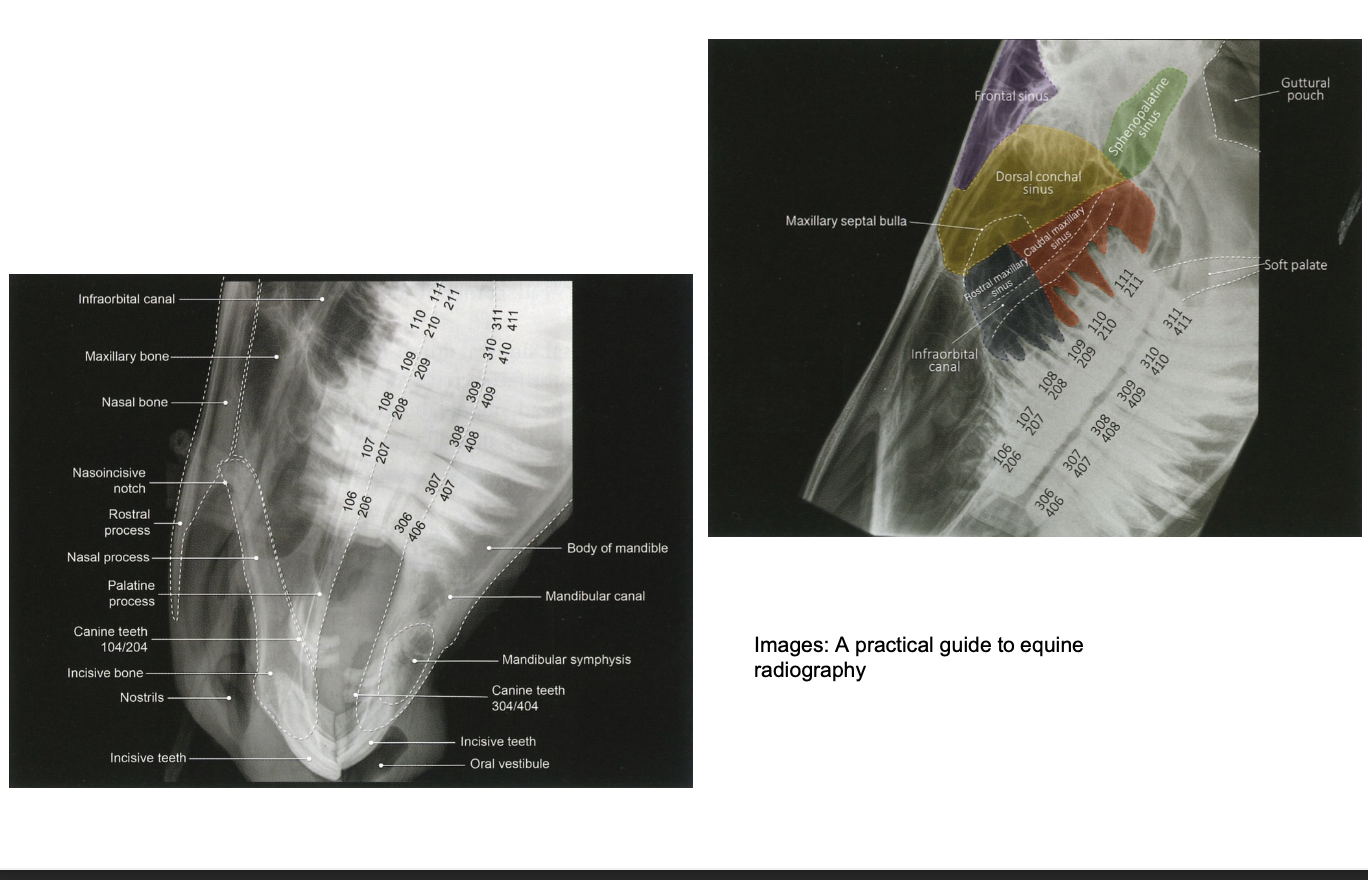

What is latero lateral view used for?

Good for assessing the paranasal sinuses, guttural pouches & pharynx

but cheek teeth superimposed on each other

Latero-lateral view anatomy for reference

When is a dorsoventral view used?

Assessment of paranasal sinuses, nasal septum & teeth

Helps to determine if lesions unilateral/bilateral

Normal dorsoventral view anatomy